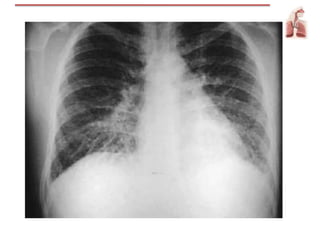

Radiografía de tórax

Bordes imprecisos

Imagen de mariposa

Cefalización

Líneas de Kerley

Oximetría / gasesarteriales Radiografía de tórax Bordes imprecisos Imagen de mariposa Cefalización Líneas de Kerley EKG / Ecocardiograma Lesión coronaria aguda Elevación de ST Aparición de onda Q significativa Hipertrofia ventrículo y/o atrio IZQ Marcadores de lesión cardiaca Cateterismo DER cardiaco